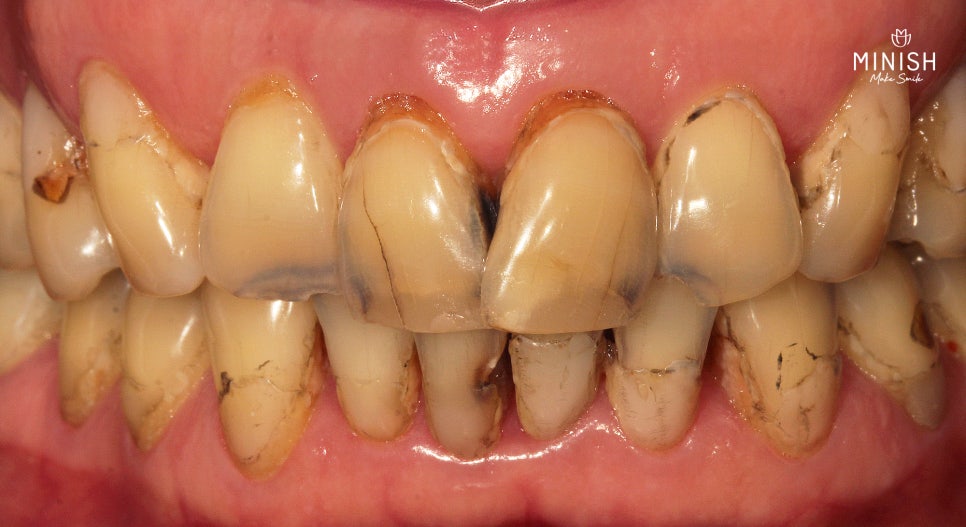

항암치료 후 다발성 치아우식증으로 치아색상이 전반적으로 검게 변하고 기능적으로도 마모와 부식으로 저작에 어려움을 겪은 고객님

50대 초반 고객님은 항암치료 이후 다발성 치아우식증으로 인해 치아 색상이 전반적으로 어두워졌으며, 마모와 부식으로 저작에 어려움을 겪었습니다. 미니쉬는 항암 부작용으로 손상된 치아를 회복하기 위한 마지막 희망이었습니다.

치료 전 고객님의 치아 상태, 잇몸과 경계가 패인 흔적, 레진 보강, 크랙으로 착색된 부분을 확인할 수 있습니다.